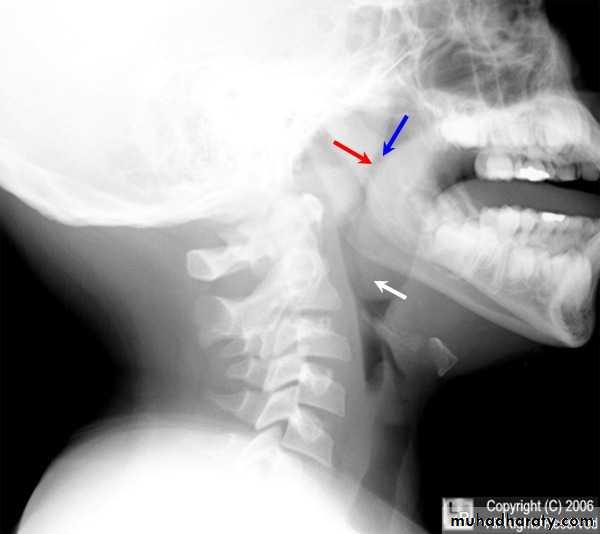

INVESTIGATION:

Lateral plain x-ray of the nasopharynx: A soft tissue shadow narrowing the airway => diagnostic.